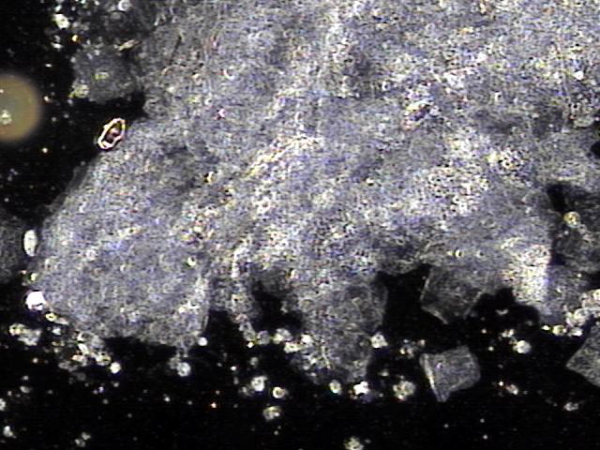

주 2회 전립선의 표적 치료중 전립선액과 정낭액 그리고 전립선 결석과 정관등에 침범하여 퍼지고 있는 균의 배양과 항생제 민감도 검사를 하기위해 표적 치료후 배출된 전립선액의 현미경 검사 자료입니다.

탈락된 상피세포 덩어리와 혈정액과 전립선 결석과 전립선암의 전암병변 의심되는 자료입니다.

This is a microscopic examination of prostatic fluid discharged during biweekly targeted prostate therapy. The sample was obtained to conduct bacterial culture and antibiotic sensitivity testing for organisms invading and spreading through the prostatic fluid, seminal vesicle fluid, prostate calculi, and vas deferens. The findings include clusters of desquamated epithelial cells, hematospermia, prostatic calculi, and features suspicious for precancerous lesions of prostate cancer.